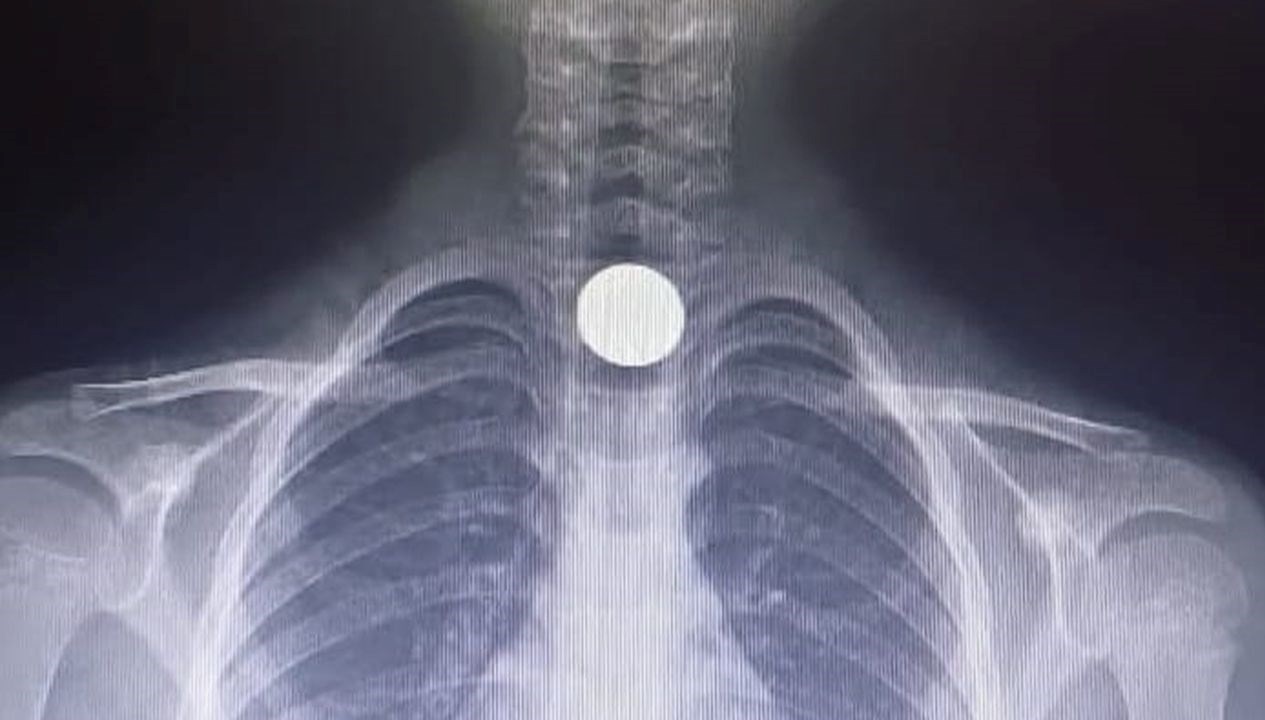

Yapılan incelemeler sonucunda yemek borusuna 50 kuruşluk metal bir para sıkıştığı anlaşılan Yusuf Z., acil olarak Bursa Yüksek İhtisas Eğitim ve Araştırma Hastanesi’ne gönderildi.

Burada gerçekleştirilen başarılı bir operasyonla Yusuf Z.’nin yemek borusundaki madeni para çıkarıldı.